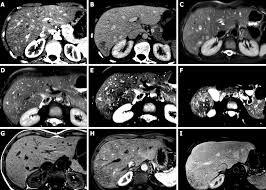

Na TC a avaliação é feita na fase pré-contraste. Avalia-se objetivamente através do valor absoluto e comparativo do ROI (diferença >5 entre fígado e baço) e subjetivamente através da visualização dos vasos.

Esteatose simulando lesões focais.

A lesão hipoatenuante próxima ao hilo hepático corresponde a área poupada de esteatose.

As lesões na imagem correspondem a esteatose multifocal/multinodular.

Esteatose focal típica no segmento IV.